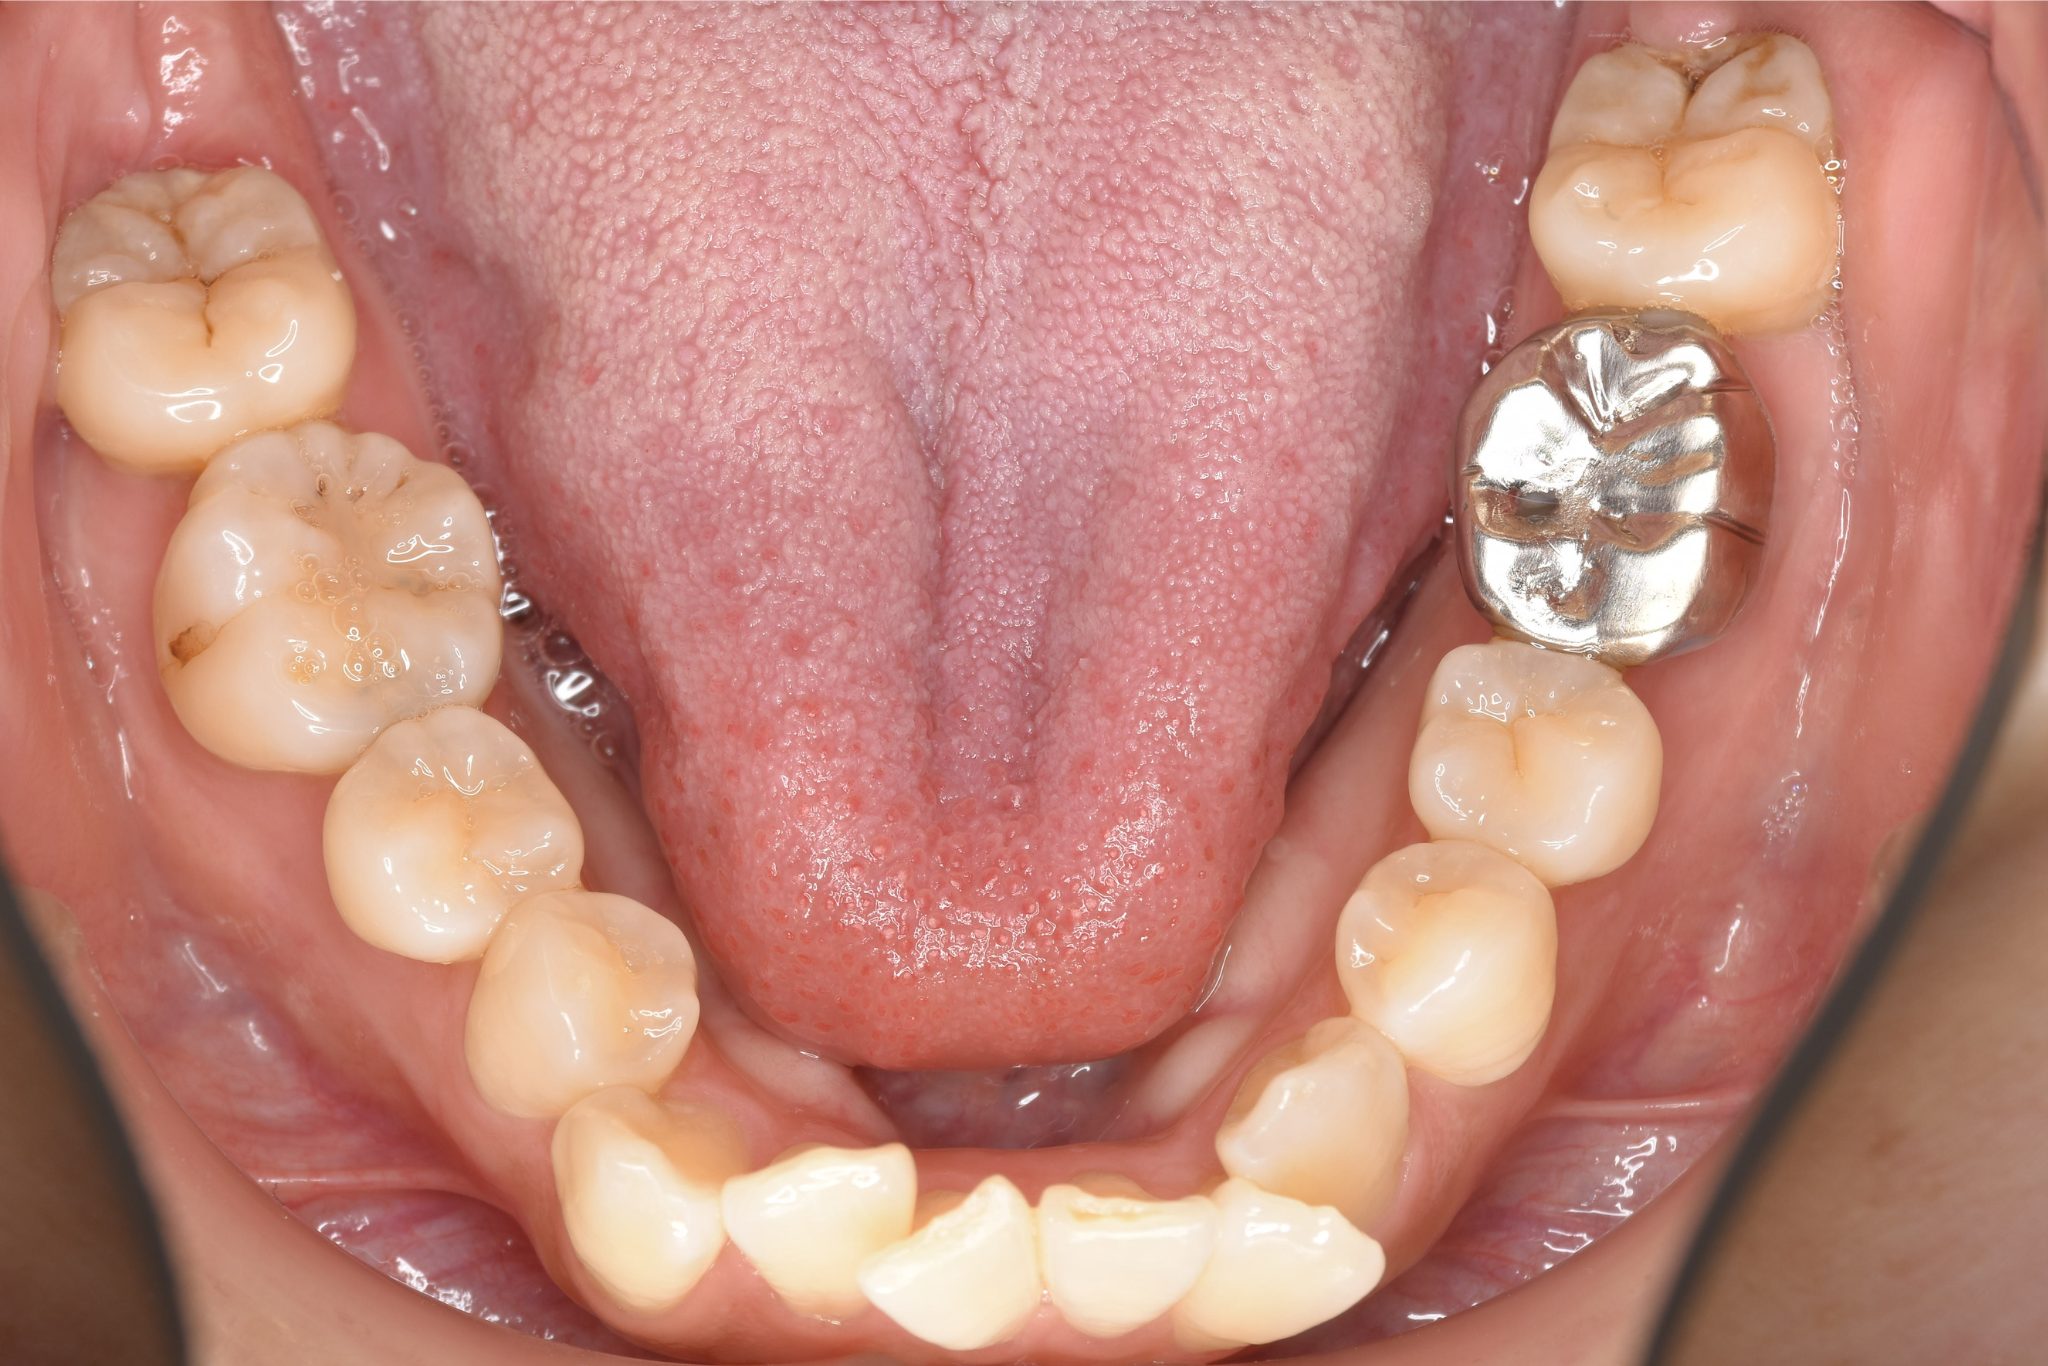

ビフォー

ワイヤー矯正治療|症例_814

主訴 八重歯

施術内容 MSEと下顎リンガルアーチを用いて上下顎骨を拡大した。

その後上顎3・4番を抜歯しマルチブラケット装置とミニインプラントを用いて

歯牙を配列した。良好な咬合を獲得した。